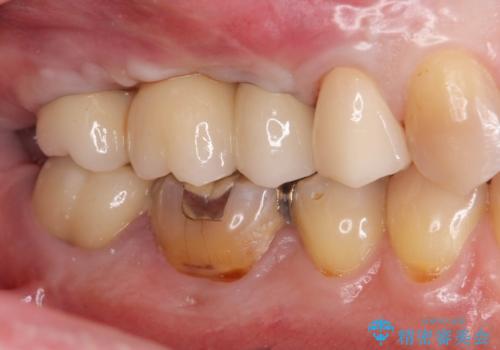

治療について

骨の造成、歯肉を整えたことで、術前山形にえぐれていた歯肉形の態はなだらかになり清掃しやすい状態へと整備することができました。